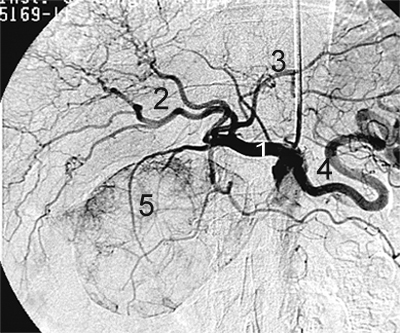

Приклади ангіограм:

стеноз правої ниркової артерії    пухлина підшлункової залози

Артерії: загальна печінкова(1),

праві печінкові (2), ліва печінкова (3),

селезінкова (4), пухлина підшлункової залози (5).